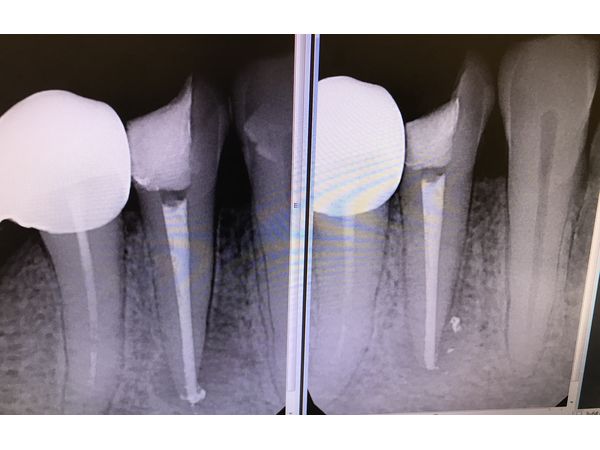

Прицельная рентгенограмма показала очаг разрушения вокруг корня зуба с нечёткими контурами.

- провели рентген-контроль, чтобы оценить качество временного пломбирования.

- провели рентген-контроль.

На контрольном осмотре через 6 месяцев прицельная рентгенограмма показала восстановление костного рисунка вокруг корня 44-го зуба и отсутствие свища. У женщины жалоб не было. Ей также рекомендовали поставить протез.